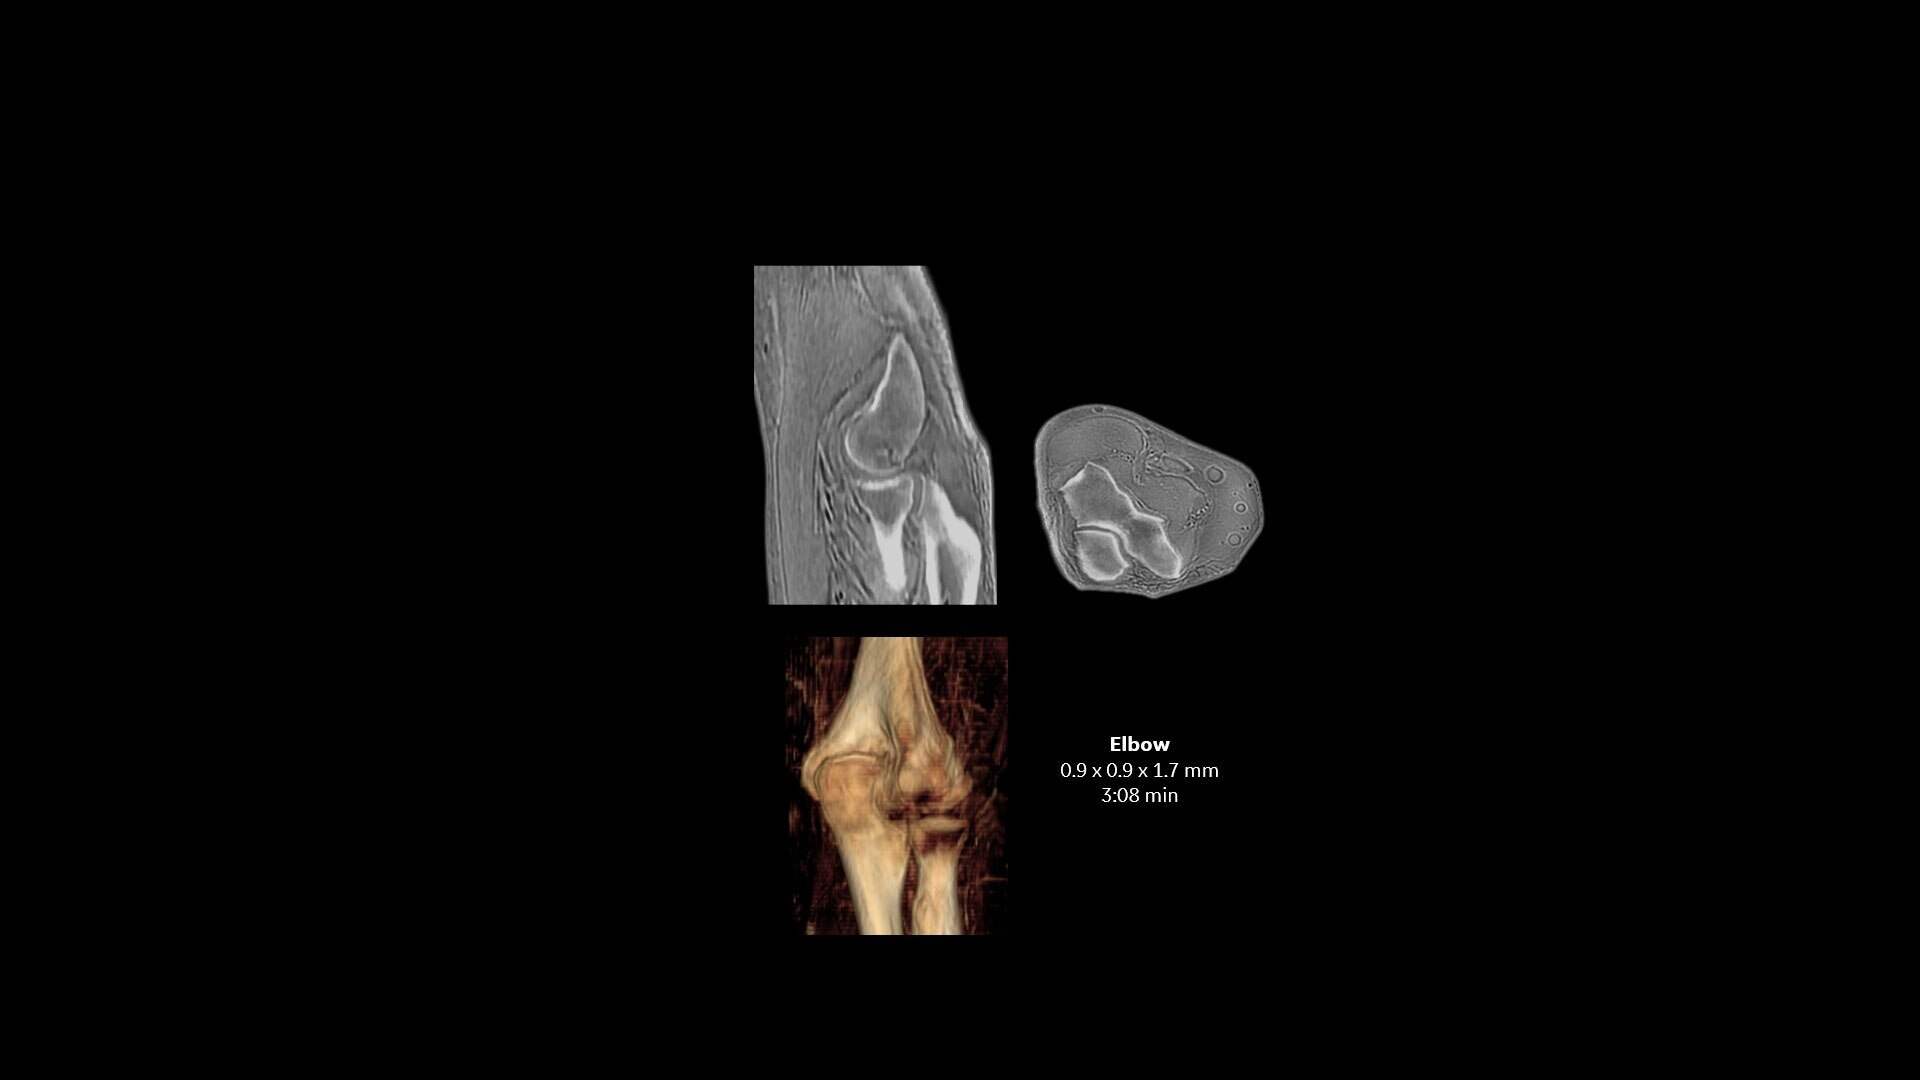

Available for all anatomies without ionizing radiation, oZTEo delivers images of bone morphology, calcification, ossification and fractures. oZTEo complements conventional MR soft tissue exams with perfect co-registration and provides 3D isotropic imaging using a radial ZTE acquisition, with inherent motion insensitivity. Use oZTEo with Volume Illumination for realistic 3D rendering.